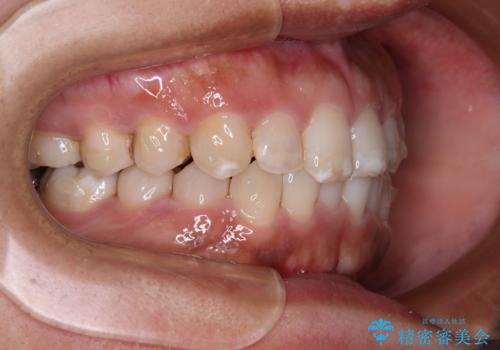

- 上下前歯の叢生を気にして来院された患者様です。

軽度な叢生であり、安価で短期間の治療を規模されていたため、インビザライン・モデレートを用いて矯正治療を行うこととしました。